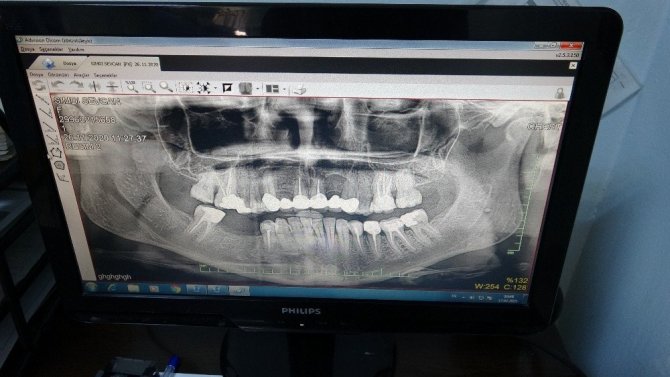

Mardin Ağız ve Diş Sağlığı merkezinde implant uygulaması Başhekim Dt. Suat Önal tarafından gerçekleştirildi. İmplant tedavisinin uygulandığı hasta Sevcan Şimdi, yapılan uygulamadan memnun olduğunu söyledi. Şimdi, "Birkaç ay önce dişimin şiddetli ağrısı nedeniyle devlet hastanesine başvurdum. Ne yazık ki geç kalmışım tedavi için. Bu yüzden implant tedavisi gerekiyordu. Özel kuruluşlar bu tedavi için çok pahalıydı. Devlet hastanesinde bu imkanlardan yararlanabileceğimi öğrendiğimde hastaneye koşarak geldim. Bu hizmeti ayağımıza getirerek bizlere sunan buna olanak veren devletimize, Mardin İl Sağlık müdürlüğümüze ve Dr. Suat Önal'a teşekkür ediyorum." dedi.

İmplant tedavisinin artık merkezlerinde yapıldığını belirten Mardin Ağız ve Diş Sağlığı Merkezi Başhekimi Dt. Suat Önal, "Halkımızın talebine karşılık vererek dental implant tedavisine başlamış bulunmaktayız. Bunun için altyapımızı güçlendirdik. Ben dahil 2 hekimimizi eğitime yollayarak dental tedavi işlemine başlamış bulunmaktayız. Dental tedavi işlemi, kaybedilen tekli veya çoklu dişlerde çene kemiğine diş köküne benzer yapıda titanyum implantların yerleştirilmesi şeklindedir. Dental tedavilerimizi dışarıdaki kliniklere veya özel kliniklere, diş tedavisi yapılan kliniklere oranla yüzde 50-60 daha ekonomik yapmaktayız. Bu sayede il dışına sekteyi epey bir azaltmayı planlıyoruz. Bu tedaviyi yapmamızda bizi destekleyen İl Sağlık Müdürümüz Uzm. Dr. Saffet Yavuz olmak üzere Kamu Hastaneleri Hizmetleri Başkanı Uzm. Dr. Murat Sinanoğlu'na ve müdürlüğümüzün tüm yönetim camiasına tüm çalışma arkadaşlarım ve şahsım adına teşekkür ederim" diye konuştu.